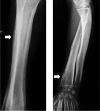

Summary: A 20-year-old man with an 8-year history of progressive enlargement of his hands and feet, coarsening facial features, painful joints and thickened, oily skin was referred for investigation of acromegaly. On examination, the subject was of normal height and weight. He had markedly increased skin thickness around the forehead, eyelids and scalp with redundant skin folds. Bilateral painful knee swelling was accompanied by enlargement of the extremities, and his fingers were markedly clubbed. Routine hematological, biochemical and hormonal blood tests, including GH and IGF-1 were normal. The clinical picture suggested primary hypertrophic osteoarthropathy (PHOA) rather than acromegaly and radiological studies were supportive of this, demonstrating increased subperiosteal bone formation and increased bone density and cortical thickening. There was widespread joint disease, with narrowing of joint spaces, whereas the knees demonstrated effusions and calcification. A skull X-ray revealed calvarial hyperostosis and a normal sellar outline. Family history was negative. Genetic studies were performed on peripheral blood leukocyte DNA for mutations in the two genes associated with PHOA, 15-hydroxyprostaglandin dehydrogenase (HPGD; OMIM: 601688) and solute carrier organic anion transporter family member 2A1 (SLCO2A1; OMIM: 601460). The sequence of HPGD was normal, whereas the subject was homozygous for a novel pathological variant in SLCO2A1, c.830delT, that predicted a frameshift and early protein truncation (p.Phe277Serfs*8). PHOA, also known as pachydermoperiostosis, is a rare entity caused by abnormal prostaglandin E2 metabolism, and both HPGD and SLCO2A1 are necessary for normal prostaglandin E2 handling. High prostaglandin levels lead to bone formation and resorption and connective tissue inflammation causing arthropathy, in addition to soft tissue swelling.